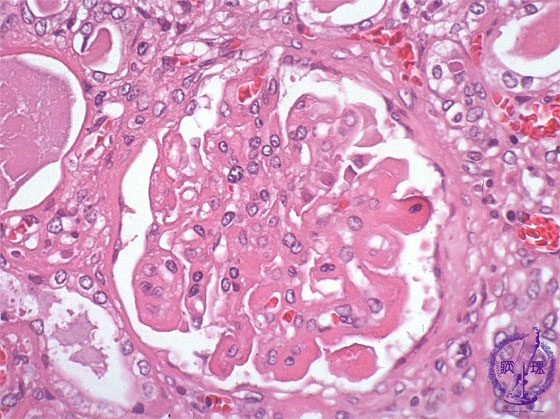

- (6)Lupus Glomerulonephritis

Microscopic findings ( HE, high power view): The basement membrane is markedly thickened and the classic wire-loop lesion is seen (blue arrows). There is focal mesangial cell proliferation.